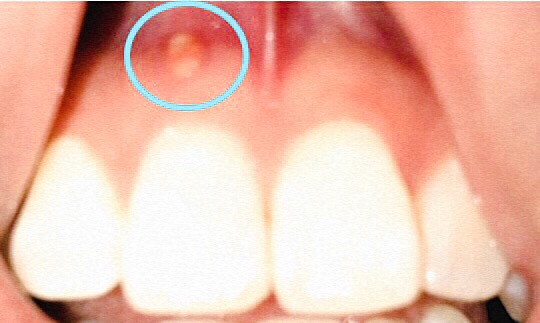

フィステルとは